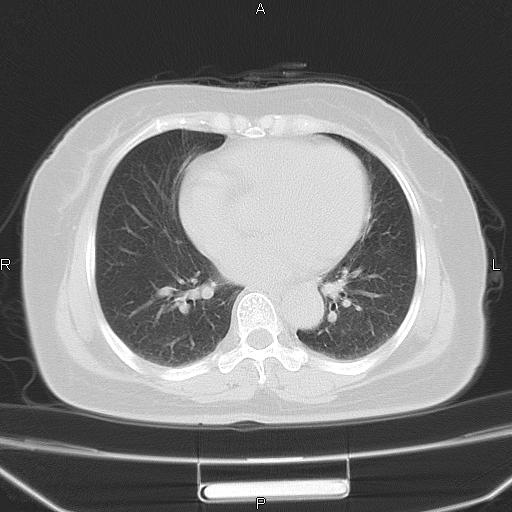

胸腺瘤

女、63Y 双眼睑下垂,早轻晚重。 胸腺瘤???

结果胸腺瘤